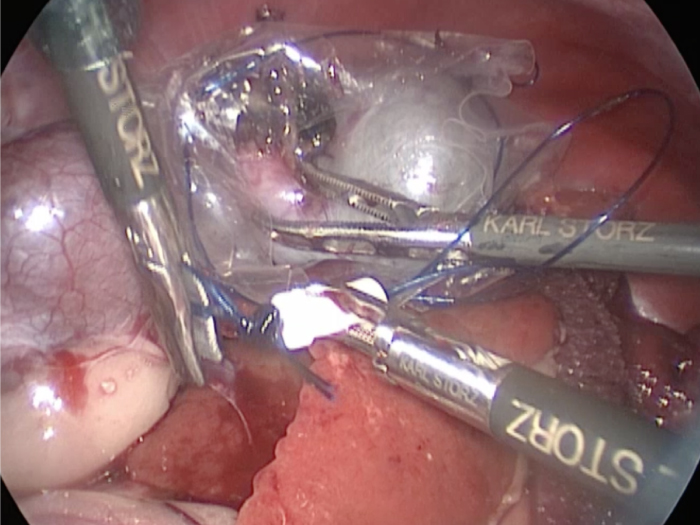

胆嚢の周囲の脂肪や膵臓、十二指腸が激しく癒着し剥離が困難な状態でした。 胆嚢は全く確認することができませんでした。

少しずつ癒着を剥がして胆嚢が確認できるようになってきました。

こんなに癒着していることはあまりないので過去に膵炎や胆嚢炎を起こし苦しい時期があったことが推測されました。

それにしてもなかなか胆嚢はでてきませんでした。

癒着(矢印)がひどく胆嚢を確認することができませんでした。

このように癒着しているときはギリギリで剥がすとひどく出血をおこすことがあるので無理にはがそうとしないで、脂肪の血管に注意しながら脂肪ごと剥がしていきます。

胆嚢の頸部に糸を通し動脈を確保しています。

胆嚢(矢印)の取り囲むように肝臓や腸が癒着していました。